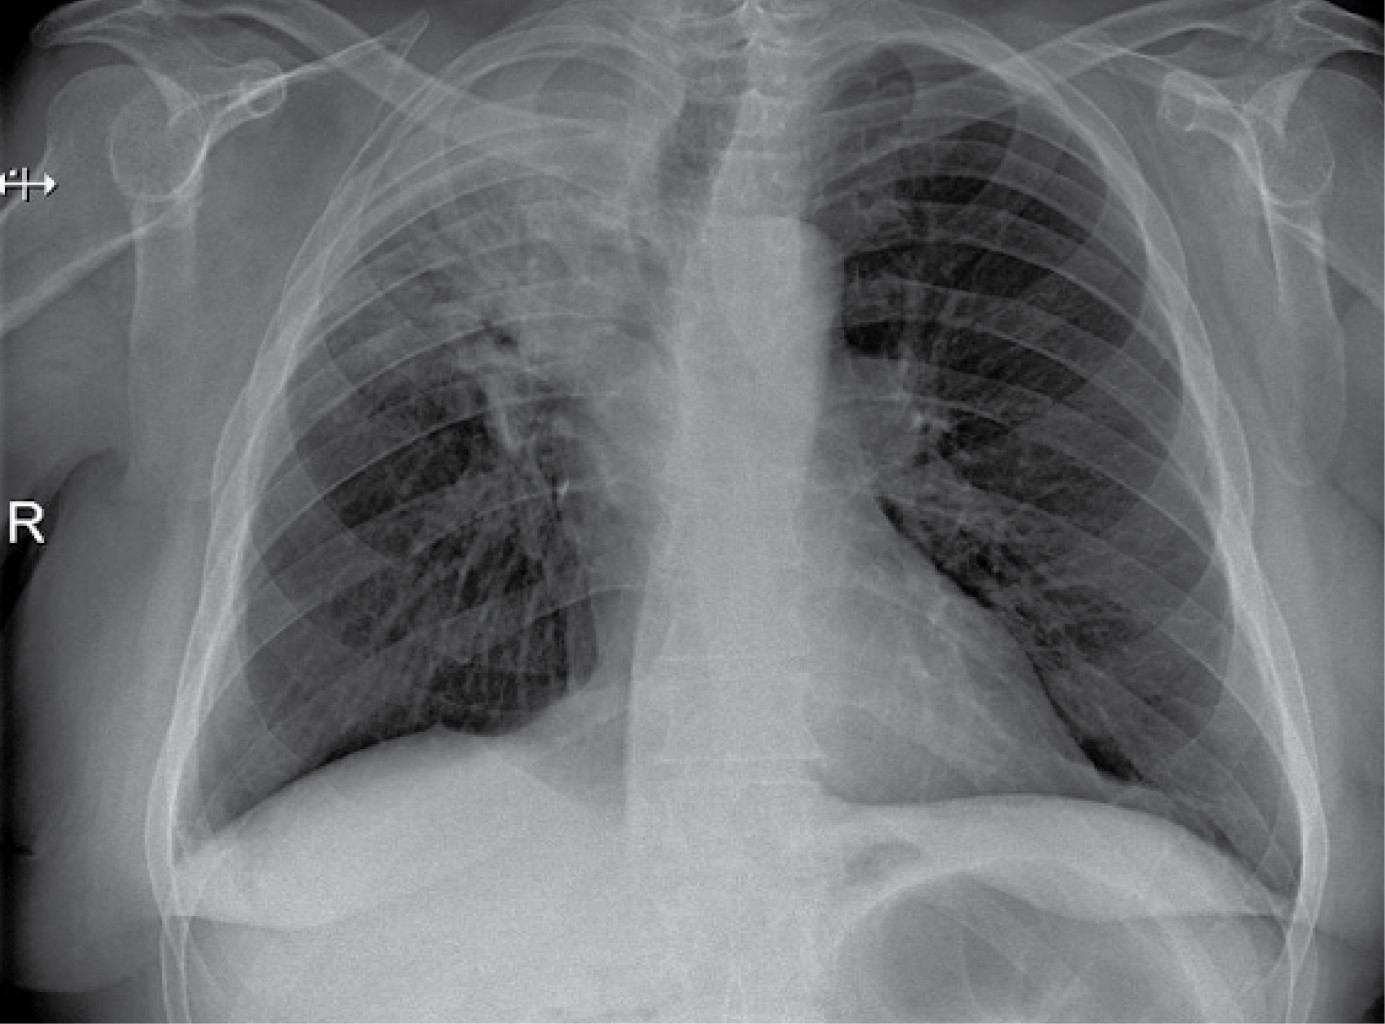

The appearance of a multiple primary malignant neoplasms is more frequent in elderly patients, lung cancer is the leading cause of cancer death worldwide, the frequency of synchronous and metachronous lung cancers has increased in recent years due to advances in early detection techniques, multiple malignancies can be classified as synchronous or metachronous according to the time of onset in relation to the first malignancie, synchronous those that appear in the first six months and metachronous as those that appear after six months. We present the case of a 66-year-old male patient with a history of right radical nephrectomy for clear cell renal cancer, who goes to the emergency department seven years later for respiratory symptoms and hemoptysis. In his study protocol, he is diagnosed with a parahiliary right upper lobe endobronchial tumor of epidermoid lineage involving the right bronchus.

Figure 1